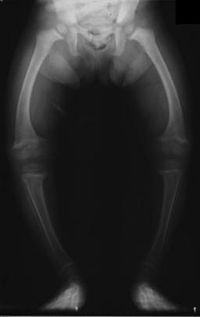

| X-Ray of the legs in a 2 year old child with rickets | |

Genu varum (also called bow-leggedness, bandiness, bandy-leg, and tibia vara) is a varus deformity marked by (outward) bowing at the knee, which means that the lower leg is angled inward (medially) in relation to the thigh's axis, giving the limb overall the appearance of an archer's bow. Usually medial angulation of both lower limb bones (femur and tibia) is involved.